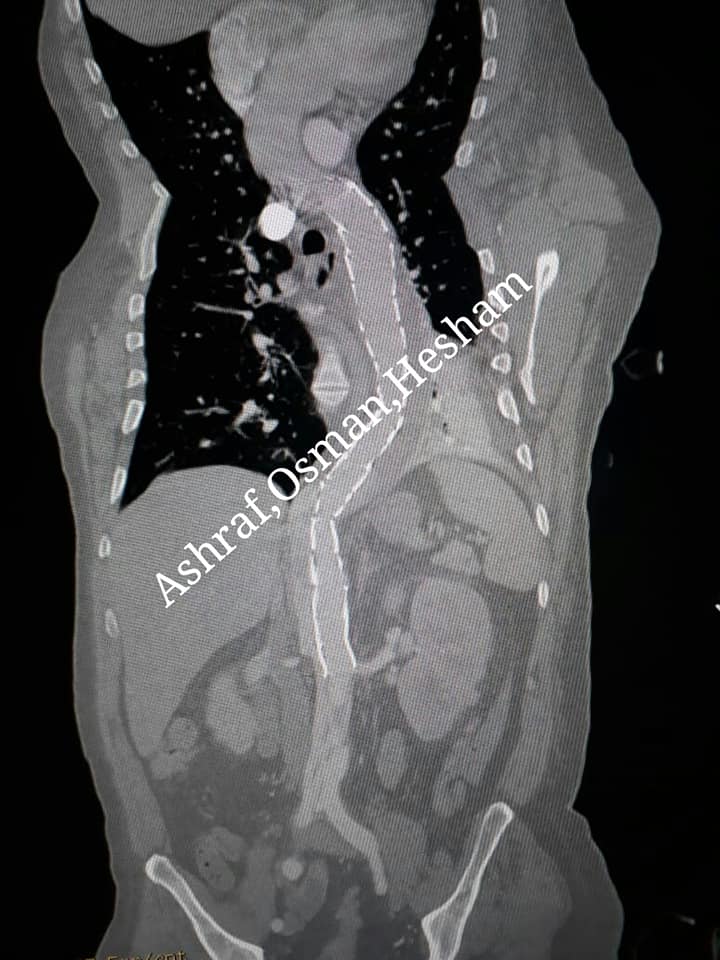

Zone 1 hybrid Aortic arch debranching plus TEVAR and dissection stents for complicated type B dissection

جامعه أسيوط وقسم جراحة الأوعية الدموية ومستشفى الأورمان الجامعي وقسم التخدير والعناية المركزة بصعيد مصر بأحرف من نور قصه نجاح اكبر عملية واخطر عملية لعلاج مريض يصارع الموت بسبب حدوث شق بالشريان الأورطى الصدري والشريان الأورطى البطى ممتدا من الشريان تحت الترقوي الأيسر وحتى الشريان الحرقفى الأيمن مسببا شلل نصفى للمريض وارتفاع شديد في وظائف الكلى أدى إلى عمل جلسات غسيل دموي لإنقاذ المريض وحدوث ارتفاع في وظائف وإنزيمات الكبد بسبب القصور في الدورة الدموية

استقبل مستشفى الأورمان مريض يبلغ من العمر 47 عام قادم بالأم شديدة بالصدر والبطن وبمناظرة المريض من قبل فريق قسم القلب والأوعية الدموية وعمل ايكو وأشعه مقطعية عاجلة أظهرت وجود شق بطول الشريان الأورطى الصدري والبطنى وقصور في الدورة الدموية لشرايين الكليتين والكبد والأمعاء وحدوث شلل نصفى

وبصوره عاجله تم إبلاغ جراحة الأوعية الدموية وبمناظره المريض والاشعات من قبل فريق جراحة الأوعية الدموية ( د هشام أبو العيون مدرس جراحة الأوعية الدموية ود أشرف النجار مدرس جراحة الأوعية الدموية و د عثمان محمود احمد مدرس جراحة الأوعية ) وعمل القياسات للشريان الأورطى وتقييم الوضع وكان الشق بجوار الشريان تحت الترقوي وعمل مسافة صغيره لا تسمح بتركيب دعامات مغطاة فقط وكان الراىء هو التدخل العاجل لعمل وصله بين الشريان السباتى الأيمن إلى الشريان السباتى الأيسر والى الشريان تحت الترقوي لخق مساحه مناسبة لتركيب الدعامات

Aortic arch debranching zone 1 hybrid debranching then TEVAR and dissection stents

وتم إدخال المريض للقسطرة وتم بنجاح تركيب دعامة مغطاة وسد الشق بالشريان الأورطى الصدري وتم تركيب دعامة تعمل على استعاده المجرى الرئيسي للدم لتسمح بتدفق الدم لشرايين الأمعاء والكبد والكلى وشرايين الحبل الشكوى مدعومة باستخدام قسطرة التصوير من داخل الشرايين (الايفوس) حتى نتمكن من تحديد وجهة الأسلاك وتحديد المكان الدقيق لتركيب الدعامة المغطاة داخل القوس الأورطى الصدري والدعامات الأخرى وذلك لصعوبة استخدام صبغه لخطورتها على الكلى وكذلك بسبب ارتفاع وظائف الكلى

Zone I hybrid debranching plus TEVAR and dissection stent for Dissection treatment and acute true lumen expansion

MESCT angio showed nicely placed stent, patent carotid carotid subclavian bypass, thrombosis of the false lumen against the covered stent with patent all visceral and renal vessels